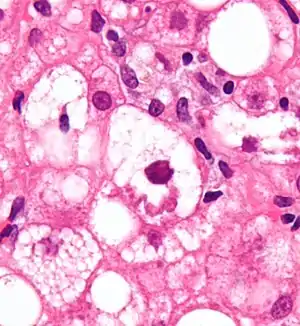

Micrograph showing a Mallory body with the characteristic twisted-rope appearance (centre of image - within a ballooning hepatocyte). H&E stain.

Mallory bodies are highly eosinophilic and thus appear pink on H&E stain. The bodies themselves are made up of intermediate cytokeratin 8/18 filament proteins that have been ubiquitinated, or bound by other proteins such as heat shock proteins, or p62/Sequestosome 1.[5]